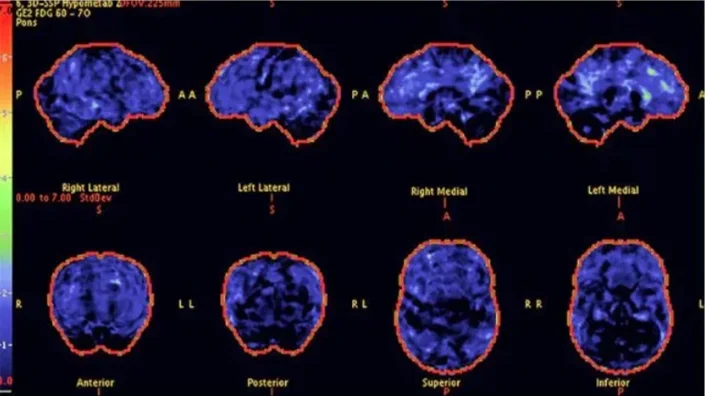

Above: PET scans show reduced brain activity in a 68-year-old woman with progressive symptoms of memory loss. The stained areas indicate low levels of acetylcholine, associated with the accumulation of invisible brain toxins.

Above: After 8 weeks with Memory Lift, PET scans show a significant improvement in brain activity - especially in the areas linked to memory retention and focus. The natural production of acetylcholine has been restored, resulting in greater clarity and cognition.